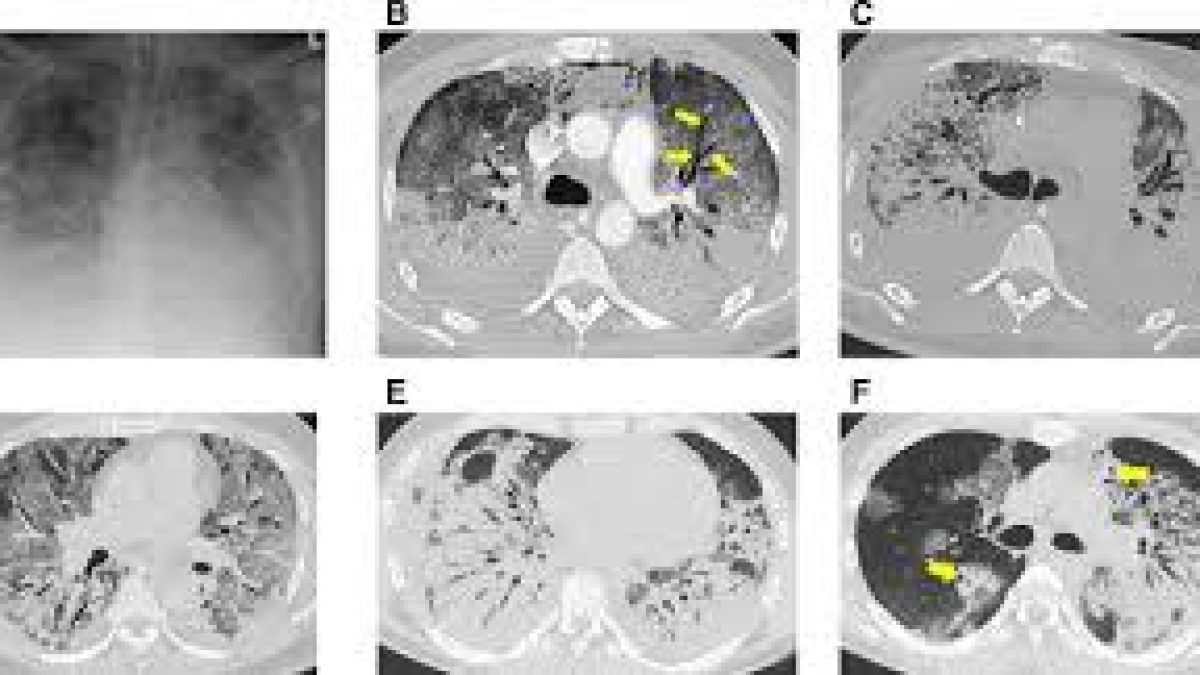

It is a medical imaging technique used in radiology to get detailed images of the body noninvasively for diagnostic purposes.

CT scanners use a rotating x-ray tube and a row of detectors placed in the gantry to measure X-ray attenuations by different tissues inside the body.

The multiple X-ray measurements taken from different angles are then processed on a computer using reconstruction algorithms to produce tomographic (cross-sectional) images (virtual “slices”) of a body.